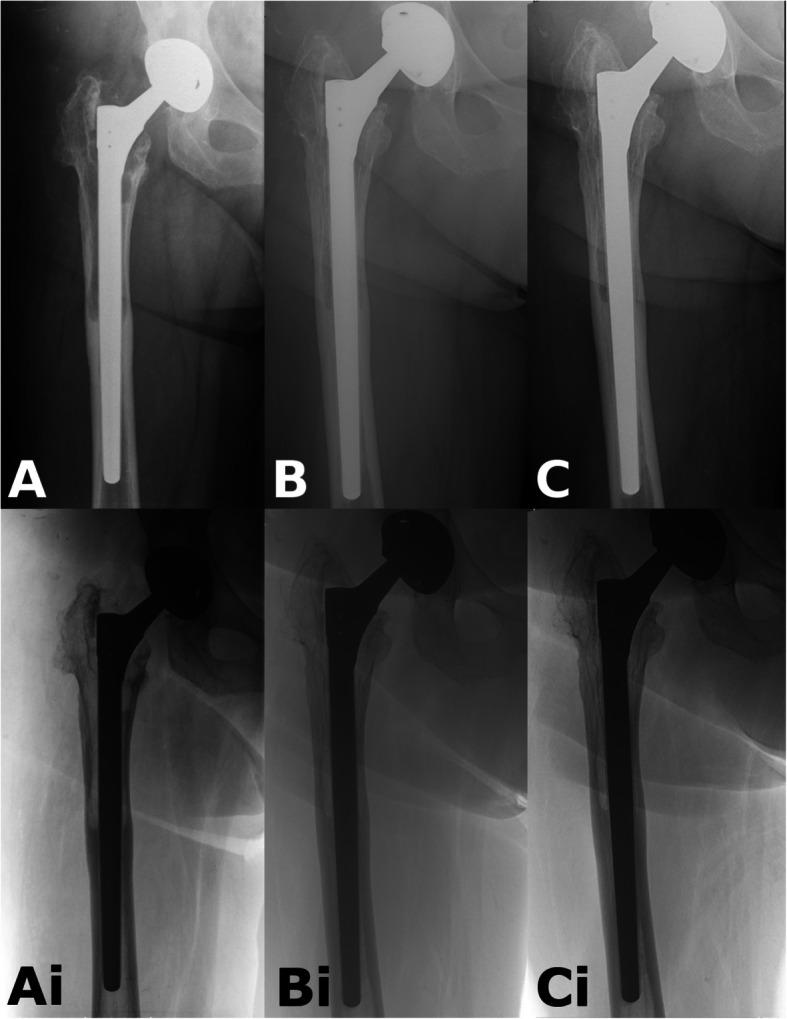

Monoblock taper fluted stems have been reliably used to treat proximal femoral periprosthetic fractures (PFF) and femoral aseptic loosening (AL). Although proximal femoral remodeling has been observed around the Wagner Self-Locking (SL) stem, the exact characteristics of this process are yet to be established. Our aim was to compare the remodeling that takes place after femoral revisions for PFF and AL.

Consecutive patients between January 2015 and December 2017 undergoing femoral revision using the Wagner SL stem for PFF or AL without an extended trochanteric osteotomy (ETO) or bone grafting were selected from our database. Radiological follow-up was performed using plain antero-posterior hip radiographs taken postoperatively and at 3, 6, 12 months and at 24 months. The Global Radiological Score (GRxS) was utilized by four blinded observers. Intra and interobserver variability was calculated. Secondary outcome measures included the Oxford Hip Score and the Visual Analog Scale for pain.

We identified 20 patients from our database, 10 PFF and 10 AL cases. The severity of AL was Paprosky 2 in 2 cases, Paprosky 3A in 2 cases and Paprosky 3B in 6. PFF were classified as Vancouver B2 in 7 cases and Vancouver B3 in 3 cases. Patients undergoing femoral revision for PFF regained 89% (GRxS: 17.7/20) of their bone stock by 6 months, whilst patients with AL, required almost 2 years to achieve similar reconstitution of proximal femoral bony architecture 86% (GRxS: 17.1/20). Inter-observer reproducibility for numerical GRxS values showed a "good" correlation with 0.68, whilst the intra-observer agreement was "very good" with 0.89. Except immediate after the revision, we found a significant difference between the GRxS results of the two groups at each timepoint with pair-wise comparisons. Functional results were similar in the two groups. We were not able to show a correlation between GRxS and functional results.

整体锥形带槽柄已被可靠地用于治疗股骨近端假体周围骨折(PFF)和股骨无菌性松动(AL)。尽管在瓦格纳自锁(SL)柄周围观察到了股骨近端重塑,但这一过程的确切特征尚未明确。我们的目的是比较PFF和AL股骨翻修术后的重塑情况。

方法

从我们的数据库中选择2015年1月至2017年12月期间连续接受使用瓦格纳SL柄进行PFF或AL股骨翻修且未进行大转子延长截骨术(ETO)或植骨的患者。术后及3、6、12个月和24个月时拍摄髋关节前后位平片进行影像学随访。由四名盲法观察者使用全球放射学评分(GRxS)。计算观察者内和观察者间的变异性。次要观察指标包括牛津髋关节评分和疼痛视觉模拟量表。

结果

我们从数据库中确定了20例患者,其中10例PFF和10例AL。AL的严重程度为2例Paprosky 2型,2例Paprosky 3A型和6例Paprosky 3B型。PFF中7例为温哥华B2型,3例为温哥华B3型。接受PFF股骨翻修的患者在6个月时恢复了89%(GRxS:17.7/20)的骨量,而AL患者则需要近2年时间才能实现股骨近端骨结构的类似重建,为86%(GRxS:17.1/20)。GRxS数值的观察者间再现性显示“良好”相关性,为0.68,而观察者内一致性为“非常好”,为0.89。除翻修后即刻外,两组GRxS结果在每个时间点的两两比较中均存在显著差异。两组的功能结果相似。我们未能显示GRxS与功能结果之间的相关性。